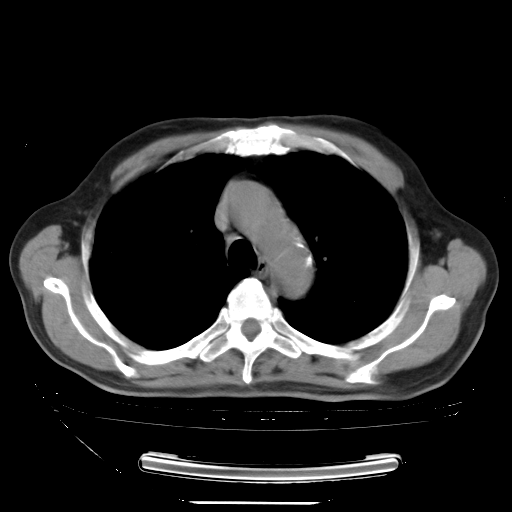

胸腹部CT,诊断意见:左上肺叶钙化灶、左侧胸膜局限性增厚并钙化、胆囊炎。描述部分肺组织呈磨玻璃样改变。